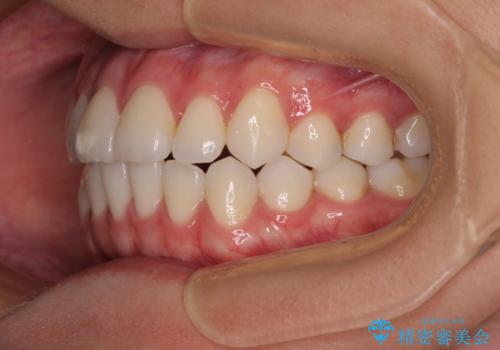

- 前歯のデコボコと奥歯の咬み合わせを気にして来院された患者様です。

右側の奥歯は、上が外側に転位した鋏状咬合を呈しており、前歯のデコボコ改善と並行して咬み合わせを改善していく必要がありました。

ワイヤー装置でもマウスピースでも、どちらでも適用の症例でしたが、片側の鋏状咬合はマウスピース矯正ではしっかりと改善できる可能性が低いことや、何と言っても自己管理の煩わしさがないことから、ワイヤー装置を選択されました。